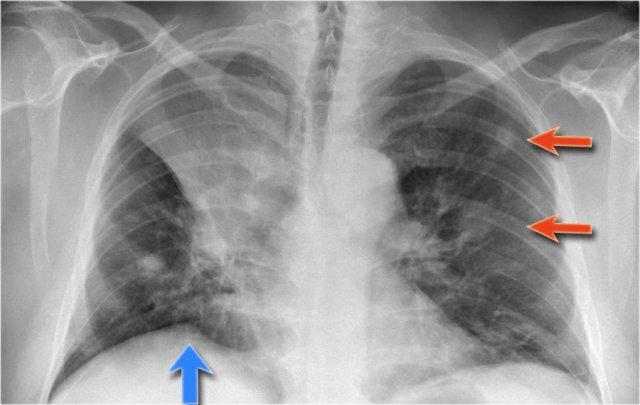

Xẹp thùy trên phổi trái

Hãy quan sát kỹ các hình X-quang trước, sau đó tiếp tục đọc.

Các dấu hiệu là gì?

- Mất thể tích tối thiểu kèm nâng cao cơ hoành trái

- Dải tăng tỷ trọng trong khoang sau xương ức, đây chính là thùy trên phổi trái bị xẹp

- Rốn phổi trái bất thường, gợi ý có thể có khối gây tắc nghẽn

- Các dấu hiệu này cho thấy xẹp thùy trên phổi trái

Các dấu hiệu bao gồm:

- Đám mờ lớn bên trái kèm mất bóng tim.

- Cơ hoành trái nâng cao kèm lều hóa.

- Khe liên thùy nhỏ ở vị trí thấp

- Rốn phổi phải ở vị trí thấp

Các dấu hiệu này cho thấy xẹp hoàn toàn thùy trên phổi trái và có thể kèm xẹp một phần phổi phải.

Do bóng bờ tim phải vẫn còn nhìn thấy được, nhiều khả năng đây là xẹp một phần thùy dưới chứ không phải thùy giữa.

Tiếp tục xem PET-CT…

Ung thư phổi bên trái gây tắc nghẽn phế quản thùy trên và ung thư phổi bên phải gây tắc nghẽn thùy dưới phải.

Trên PET-CT ghi nhận khối u ở cả phổi trái lẫn phổi phải.

Bệnh nhân có nhiều di căn xương.

Một ổ di căn xương sườn được chỉ ra bằng mũi tên.